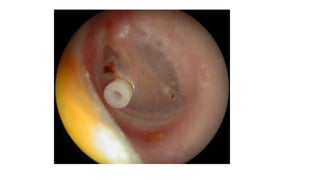

This document provides an overview of various instruments and implants used in ear, nose, and throat (ENT) examinations and surgeries. It includes images and descriptions of common ENT tools such as nasal speculums, laryngoscopes, suction nozzles, ear speculums, tracheostomy tubes, and more. The document serves as a reference for the various medical devices involved in ENT procedures.